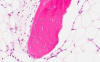

Hematoxylin & eosin

Area 2: These images illustrate the ossifying process of the shell of the lesion.

• The nodule is composed of a calcified shell of bone and scant islands of cartilage (not shown in this image). The internal part of the nodule is composed exclusively of mature adipose tissue and calcifying bone. No fibrous proliferation of inflammatory cells are present. No mature bone marrow elements are found.

• Although the overall pathologic findings are suggestive of myositis ossificans, there is no fibrous tissue proliferation at the internal part of the nodule. Instead, there is only mature adipose tissue.

• The overall finding is most consistent with a lipoma with ossification, also known as osteolipoma. Although lipoma is a fairly common condition, osteolipoma is quite uncommon. They are more likely to occur if there is local irritation such as inflammation around the lipoma.